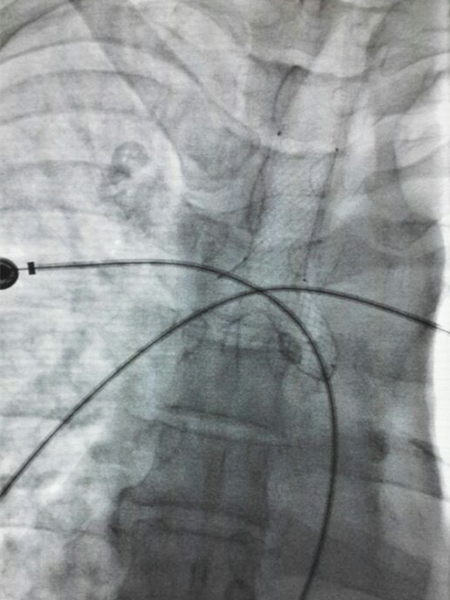

我院胸外科以李少民教授、张晋主治医师等组成的治疗团队,利用气管带膜支架置入术对该例患者进行治疗,取得满意效果。术中利用支气管镜直视下向左、右主支气管分别置入金属导丝,利用X线透视确定位置无误。

沿着导丝将“Y型”气管带膜支架的两个臂逐渐置入两侧主支气管。确认位置无误后退出导丝,再次确定支架位置。左侧支架远端为盲端,封堵瘘口,右侧支架远端通畅,维持右侧支气管系统通气功能。